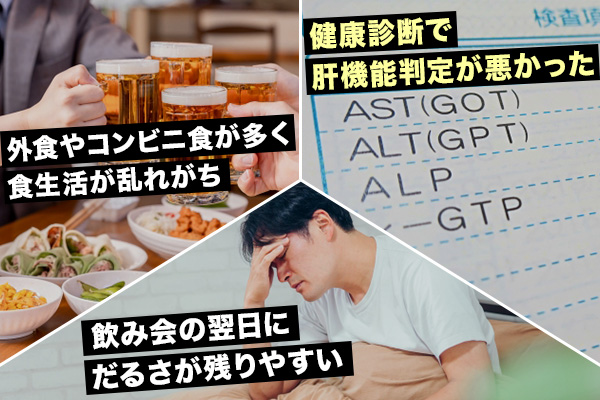

飲み会の翌日に“だるさ”が残りやすい

外食やコンビニ食が多く、食生活が乱れがち

健康診断で肝機能判定が悪かった...

一つでも当てはまる方は、肝臓に負担がかかっているかもしれません!!